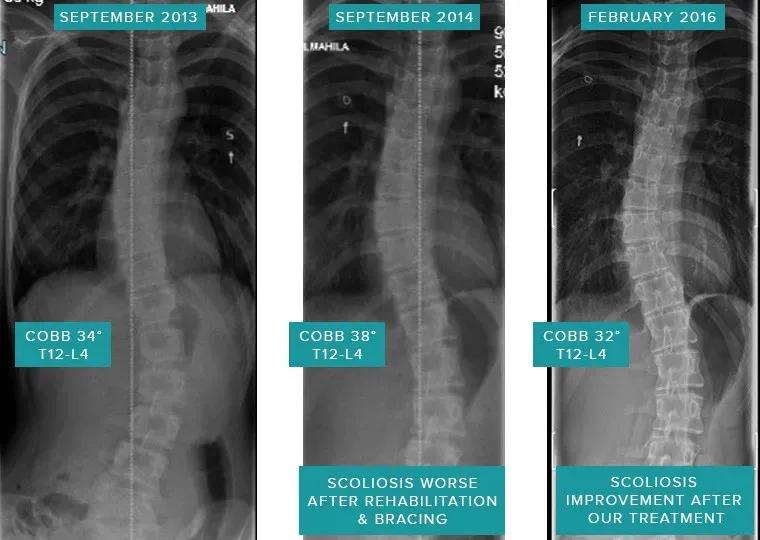

该患者年龄为40岁,胸部和腰椎40°Cobb S形脊柱侧弯,在其12岁时,就发现了脊柱侧弯。她的脊椎退化,有三个椎间盘突出,椎骨和椎间关节畸形。患者的下背部在坐下、站立、行走和躺下时翻身时都会感动疼痛。该患者在各种诊所接受了康复治疗,但没有任何改善。物理治疗师对患者进行了锻炼,这使她更加痛苦。患者的骨科专家建议对整个脊柱进行脊柱融合手术,该患者担心术后并发症,选择了非手术治疗,于是开始进行螺旋稳定治疗。

在进行了3个月的螺旋稳定训练之后,患者下背部疼痛明显减轻。经过6个月的螺旋稳定度训练后,疼痛完全消失,并开始像正常人一样工作。

T12-L4 38°Cobb-> 32°Cobb(提高6°)